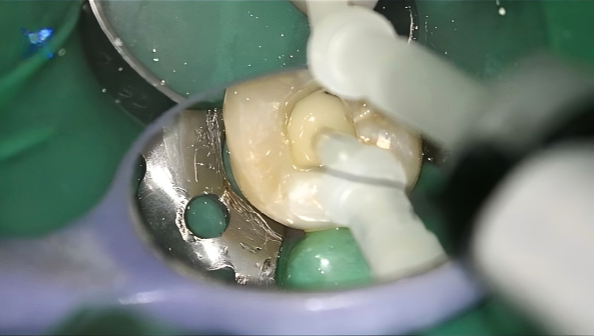

4. Core Build-Up

A dual-cure core build-up material UltraCore (HUGE) was injected and shaped anatomically. The dual-curing mechanism ensured complete polymerization throughout the core.

5. Finishing and Final Appearance

Core material was fully cured and then refined to re-establish proper anatomical contours. The restored surface showed smooth integration with the surrounding tooth structure, and the overall appearance was natural and consistent with adjacent dentition.